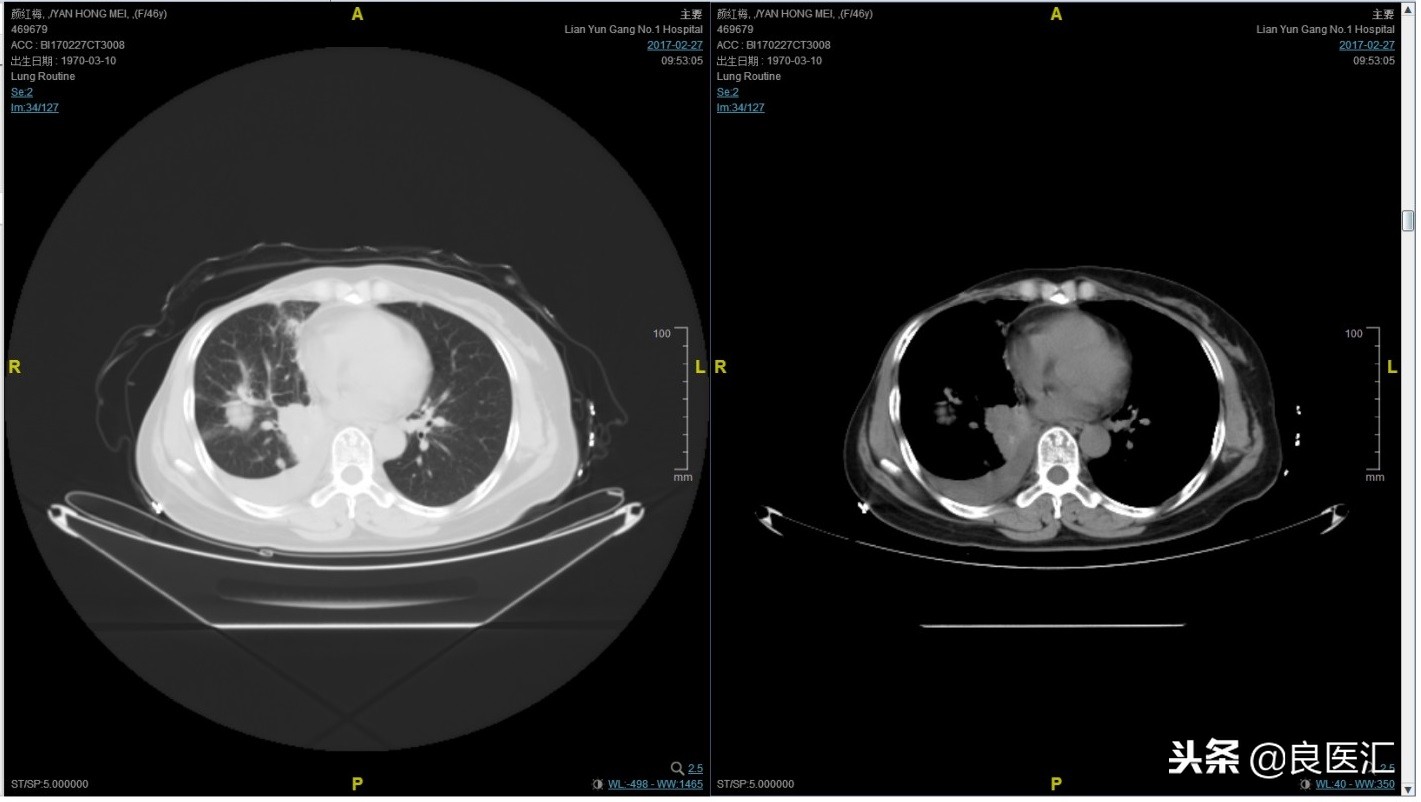

第四次复发

2017-02-27患者因气喘胸闷再次就诊。患者肺部病灶进展,同时出现肝脏转移。再次给予曲妥珠单抗+长春瑞滨化疗一周期,效果不佳,推荐换用TKI治疗,患者放弃治疗。PFS3=12个月。